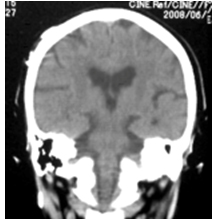

特発生正常圧水頭症のCT画像

特発生正常圧水頭症の特徴的CT所見(通常は脳を水平に撮影しますが、冠状に撮影した画像のほうがより特徴を捉えることができます)

- 脳の上のほうの隙間が狭い

- 前頭葉と側頭葉の隙間が大きく開く

- 局所的に大きな脳の隙間がある

- V字型になる(正常では直線に近い)